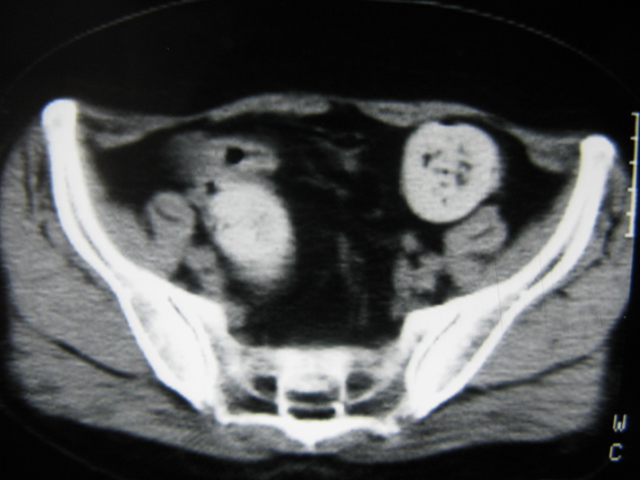

患者,女,64岁,2002年诊断为宫颈癌,当时只做过放,化疗。现在诊断:(1)宫颈癌。(2)直肠癌。请同道们讨论,探讨。另外肠壁为啥密度这么高,ct值约112hu。患者没有做过增强和造影。

高密度的不是肠管影,是肠管内的粪便影

患者直肠病变,排便不畅,粪便硬结造成,更高密度如钡灌肠者都可出现

硬结粪便能有如此高密度影?

我也碰到过几例,最离奇的一例是全结肠呈造影样高密度,患者直肠癌(首次发现),以往没有吃药,只有约半年时间长的胃纳差,排便不畅(据患者说每次大便只能拉出少许黄水)

不一定有意义,可清洁灌肠后复查